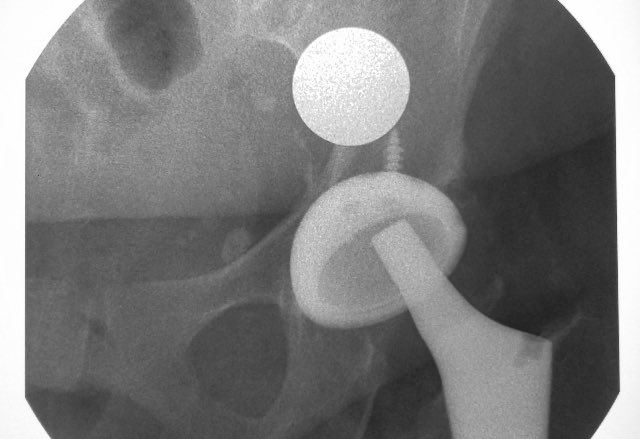

@aschwartz45 @generalorthomd Those are tm modular sockets, not continuum. Will need trilogy liners

Implant ID? Is this the Zimmer one that has NOT been recalled? Currently asymptomatic